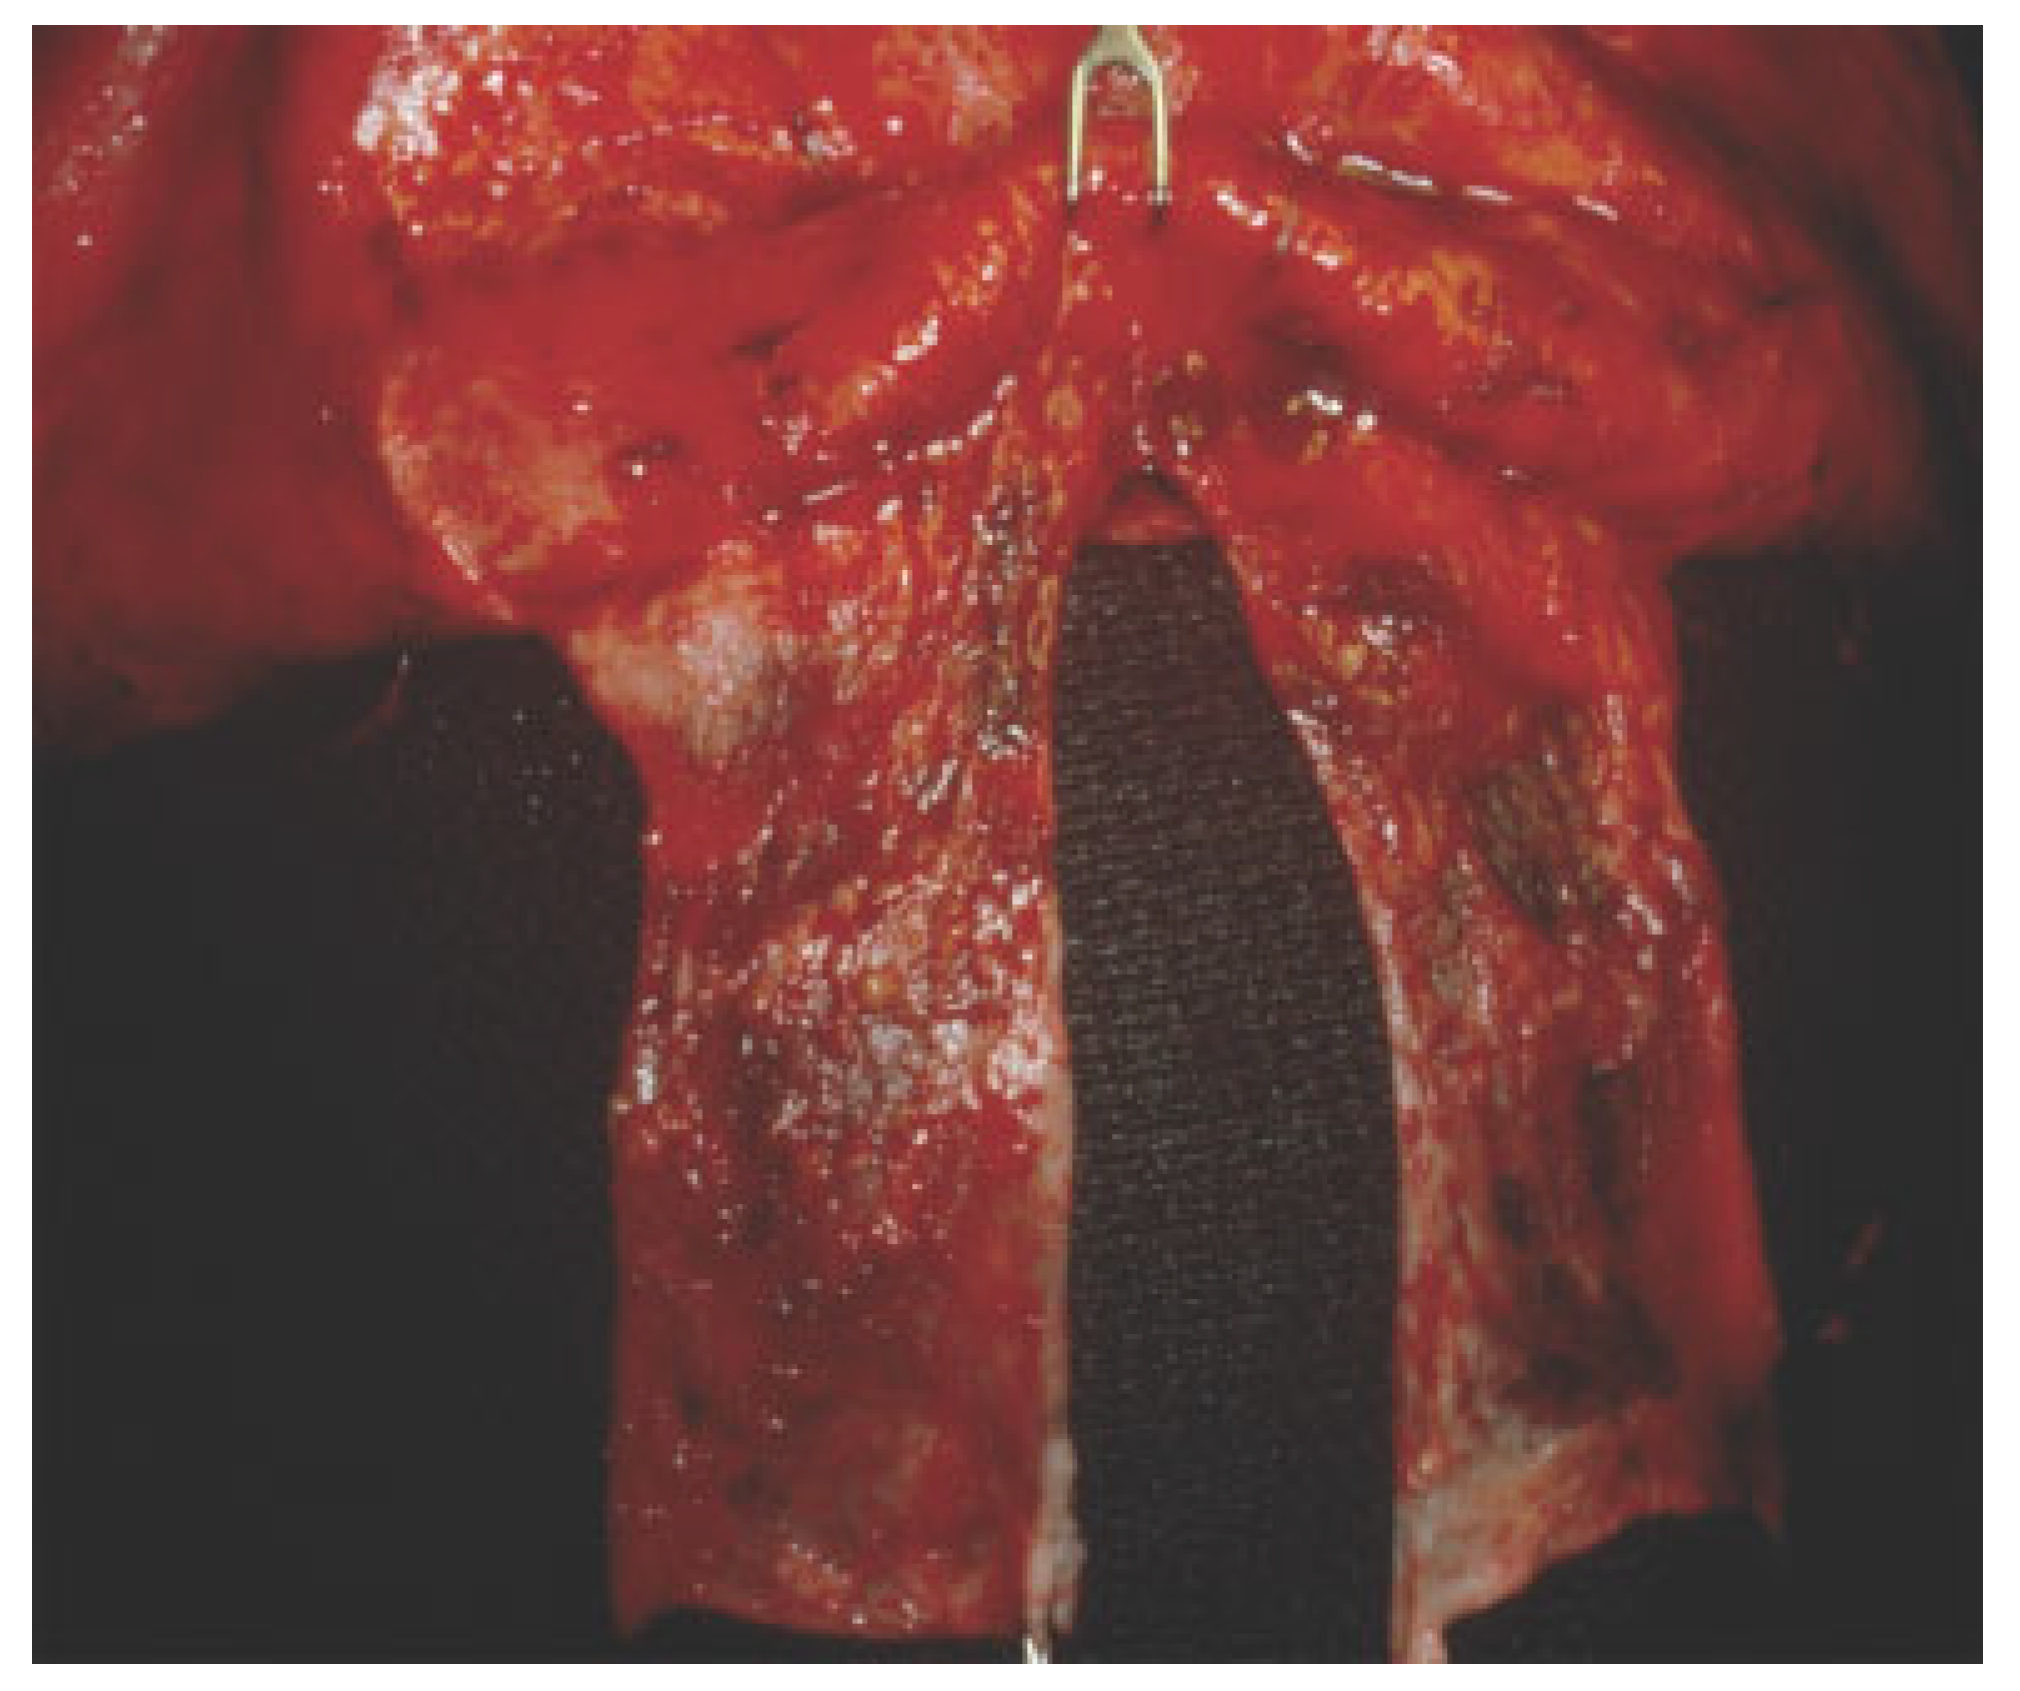

For isolated displaced anterior table fractures, standard reduction and rigid fixation is sufficient. Low profile 1.0-mm microplates are used in palpable areas. If frontonasal duct injury is suspected, the duct is first examined for patency prior to fixation. Fragments are disimpacted and removed to visua- lize the base of the sinus frontonasal ducts. Methylene blue is injected into the duct with a polyethylene catheter and a cotton tip applicator or cottonoids are placed into the nose near the middle meatus (Figure 3a). If dye is detected, the frontonasal ducts are patent (Figure 3b). If no dye is visualized or if significant doubt exists about frontonasal patency, the sinus should be obliterated. Frontal sinus obliteration is defined as obliteration of the aerated frontal sinus cavity during the maintenance of intact bony walls. Sinus mucosa is removed and mucosal curettage is performed with high speed burr. Attention is directed particularly along the posterior sinus wall toward the foramina of Breschet. The frontonasal duct can be pluggedwitha pericranial flap[15] (Figure 4). The optimalmethod for frontal sinus obliteration has been the subject of great debate. Many graft options exist including fat, dermis, fascia, muscle, bone, and alloplastic material such as silicone, Surgicel, and hydroxyapatite.[16,17,18] However, alloplastic material is not recommended because the surgical site is considered a con- taminated area and the increased risk of postoperative infec- tion. Spontaneous osteoneogenesis has been described for frontal sinus obliteration in which nothing is placed in the sinus to allow fibrous tissue ingrowth and formation of new bone.[19] In the experimental setting, the obliteration is often incomplete and complicated by infection. Rohrich and Mickel compared frontal sinus obliteration using fat, muscle, bone, and spontaneous osteoneogenesis in a cat model and literature review found no differences in the material used.[20] They concluded that successful obliteration of frontal sinus by either spontaneous osteoneogenesis or the implantation of autoge- nous fat, muscle, or bone depends on meticulous extirpation of the frontal sinus mucosa with the aid of an operating micro- scope, removal of the inner cortex of bone, and permanent occlusion of the nasofrontal duct.[20,21] Cranialization should be considered when the anatomic barrier between the sinus and intracranial cavity has been disrupted secondary to fractures of the posterior wall and dural tears.[22] Cranialization involves removal of the entire posterior sinus wall and debridement of all sinus mucosa, followed by frontonasal duct blockade with pericranial flap and/or autogenous bone (Figure 5a–d).

Figure 4. Intraoperative view of frontal sinus with pericranial flap.